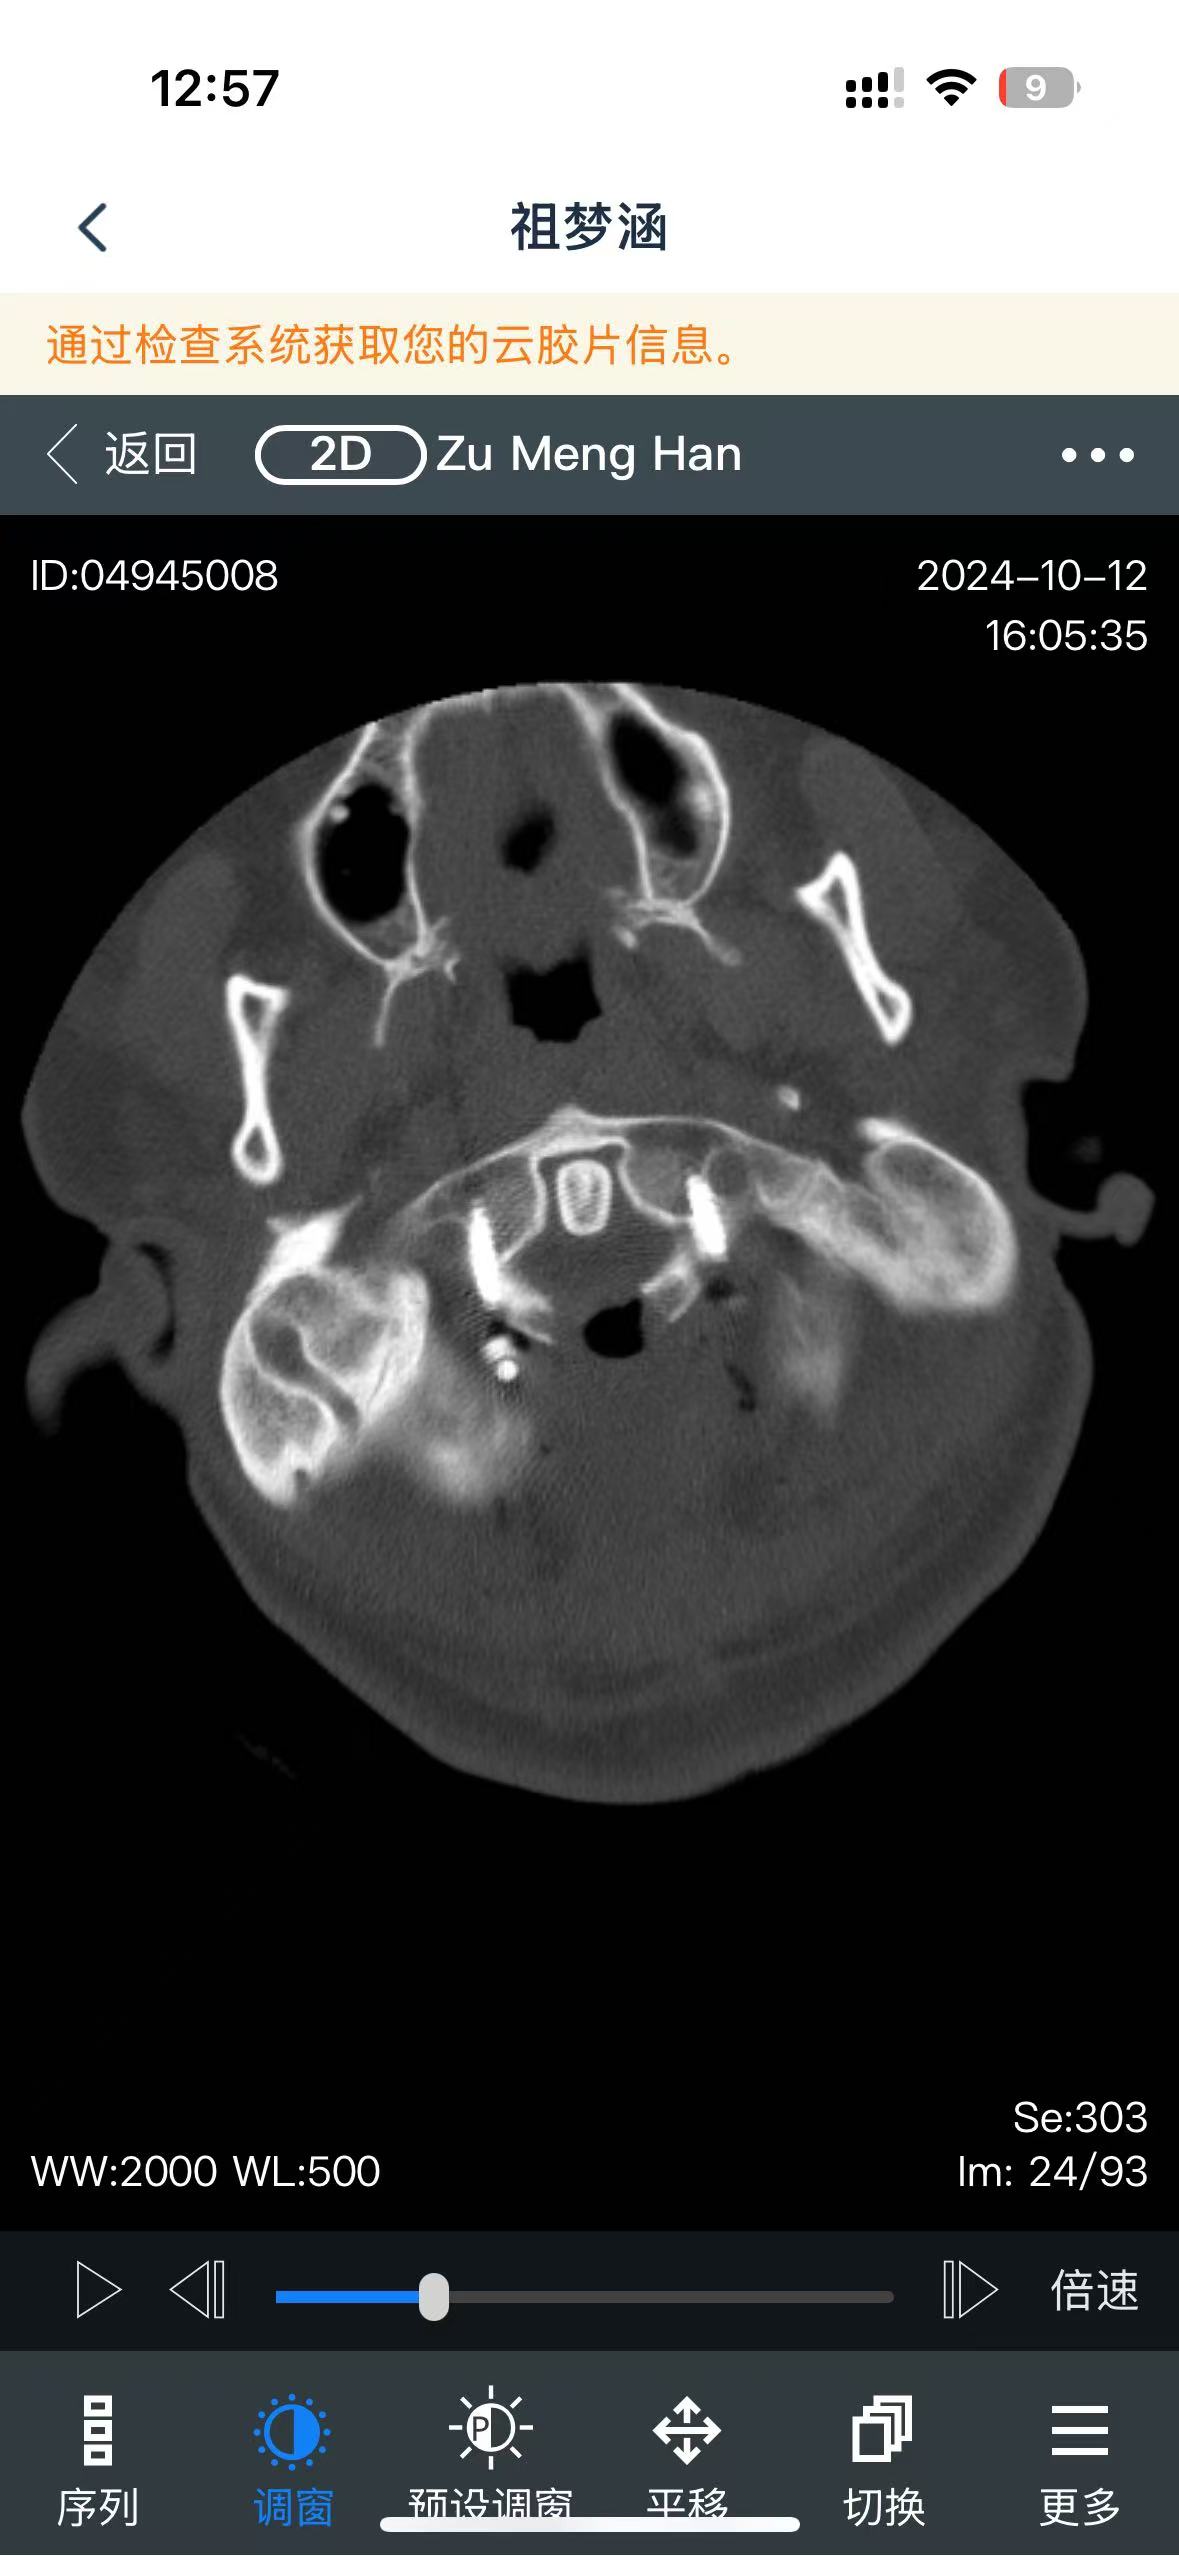

• 诊断:寰枢椎脱位

• 影像:

• 术后状况:术前患者同意不放融合器,术中切了后宫,术后复位还不错

• 术后影像: